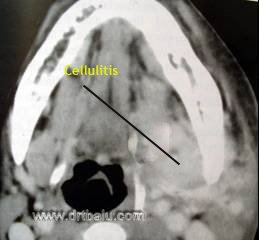

CT scan of a patient with Ludwig's angina

Diagnosis of Ludwigs angina is based on the clinical features enumerated above. These patients may show leukocytosis. X ray soft tissue neck may show soft tissue oedema. CT scan neck is to be considered in all persistent cases to rule out complications. Xray chest must also be considered to rule out mediastinitis.